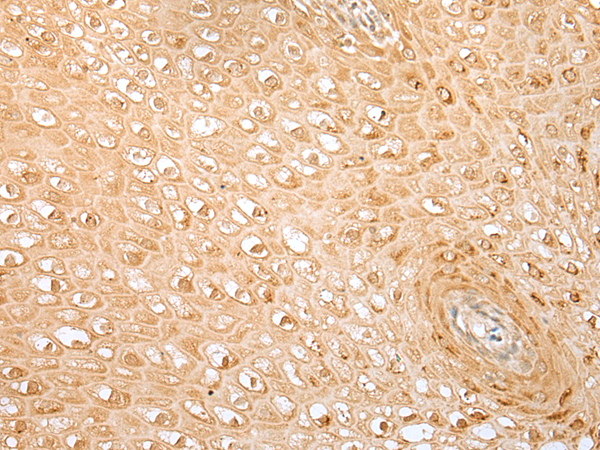

分类: 科研抗体货号: P01968别名: HCG-1; PNSC1应用: IHC反应种属: Human, Mouse, Rat